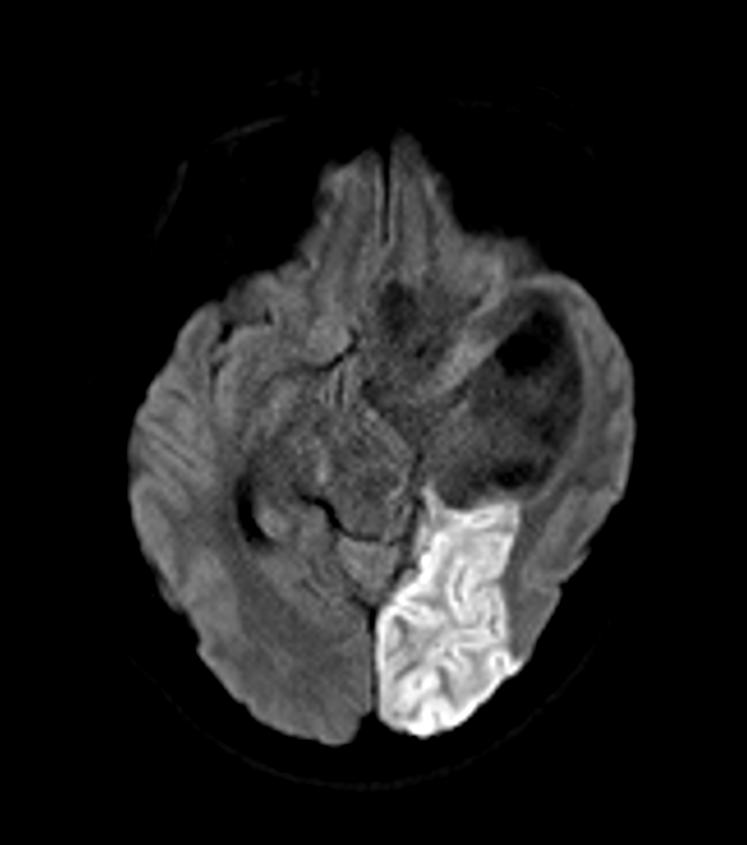

Posterior Cerebral Artery (PCA) infarct

Imaging

- MRI:

- Diffusion-weighted imaging (DWI): early detection of acute infarction

- T2-weighted and FLAIR: hyperintense signal in affected areas